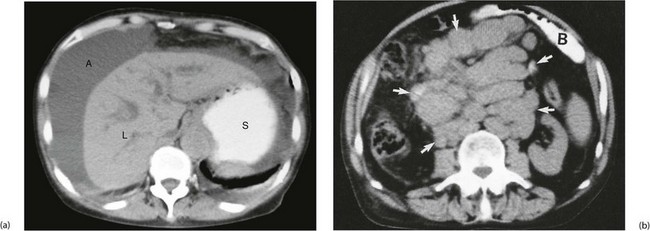

Fig. 18.14 CT scans showing gross ascites and enlarged lymph nodes

In (a) note the darker grey homogeneous shadow of fluid A around the liver L and the contrast in the stomach S. (b) Retroperitoneal mass of lymph nodes due to lymphoma. This CT scan was taken to assess the stage of spread of a known lymphoma. This 40-year-old woman presented with a large rubbery lymph node mass in her neck and was also found to have a large central abdominal mass. Abdominal CT scanning showed an enormous mass of lymph nodes (arrowed). Small bowel B is seen anteriorly, enhanced by orally administered contrast material